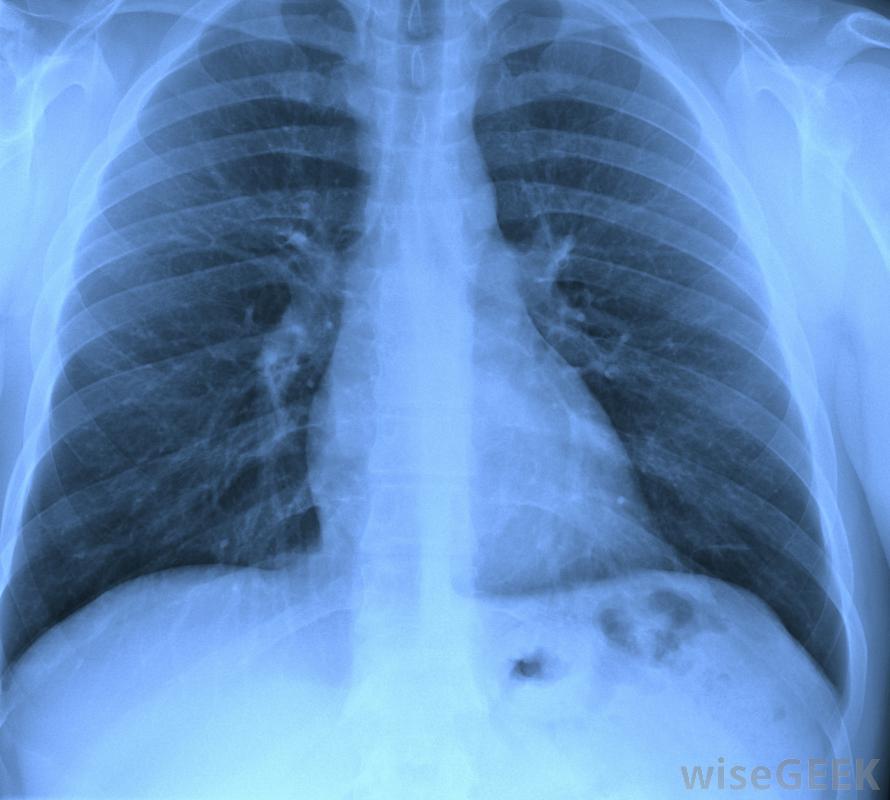

医生可能会开鼻喷雾剂大多数慢性咳嗽是由胃酸反流、鼻后滴漏、过敏或哮喘引起的。其他原因包括接触刺激物,如有害化学物质或杀虫剂、支气管炎、呼吸道感染、肺癌或对血压药物的反应。支气管扩张,肺部无法排出的严重病症粘液也可能是罪魁祸首。

慢性咳嗽可导致失眠;然而,也有一些危险因素会增加一个人患上慢性咳嗽的机会。女性比男性更容易患上慢性咳嗽,因为她们的咳嗽反应比男性更敏感。吸烟者和吸入二手烟的人一样,更容易患慢性干咳虽然人们经常不愿意向医生寻求帮助,比如咳嗽,但是慢性咳嗽不解决会导致严重的并发症。如果不治疗,慢性咳嗽会导致尿失禁、头痛、大汗和头晕例,甚至可能导致肋骨骨折。医生通常可以在一次就诊中诊断出慢性咳嗽的原因。如果不是,则可能需要进行某些检查,如胸部x光片、鼻内窥镜或窥镜检查来确定病因确定原因,制定治疗计划慢性咳嗽的治疗将取决于所做的诊断。如果咳嗽的原因是常见的鼻后滴漏,可以开抗组胺药和减充血剂。哮喘患者可以在离开医生的办公室时拿到一张吸入器或鼻喷雾剂的处方,而胃酸反流的患者可以服用降酸药物